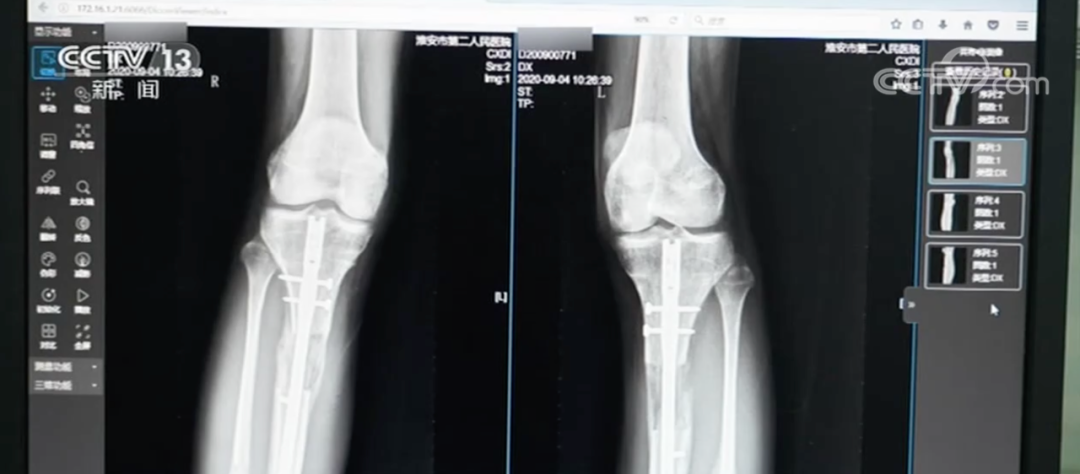

2020年,江苏省淮安市第二人民医院接诊了一名特殊患者。这名患者在国外做了“断骨增高手术”,结果导致双腿严重感染无法行走,甚至面临终身残疾。

胫腓骨延长术又叫“肢体延长术”,在医美领域,也被称为“断骨增高术”。据医生介绍,“断骨增高手术”是根据肢体组织在一定的力量刺激下可以再生的原理,把小腿或大腿的骨头“断开”,然后在体外安装具有牵伸作用的外固定支架,每天不超过1毫米的速度,将肢体缓慢延长到满意的长度。

首先,由于外固定“增高器”的16条钢针要分别穿透患者的双腿,稍有不慎便可能损伤腿部的血管、肌肉和神经组织;如果钢针消毒不好,可能会造成穿孔感染、引发骨髓炎,造成残疾。